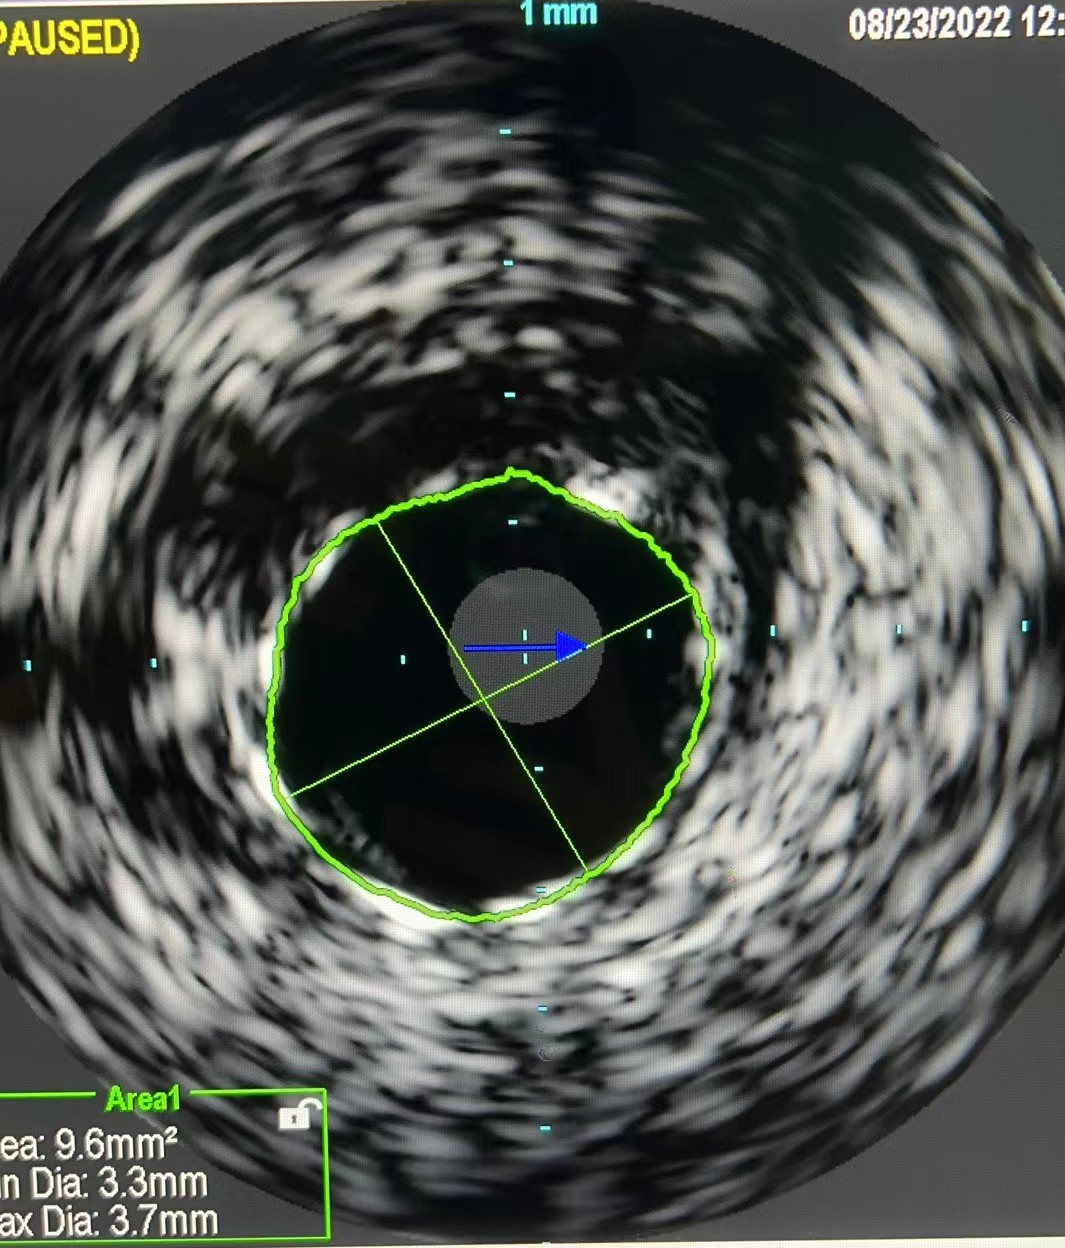

患者男性,63岁,既往糖尿病肾病,慢性肾功能不全规律血液透析,RCA曾行PCI。本次因为心力衰竭入院,入院后超声提示左室EF 仅有24%,伴有中量二尖瓣反流,冠状动脉造影提示:右优势型,血管走行区可见重度钙化影,LAD 中段次全闭塞,LCX近端重度狭窄;RCA支架内再狭窄,支架近端及远端均存在重度狭窄。患者拒绝CABG,遂在IABP的支持下,首先处理LAD。本次择期处理RCA病变,由于RCA近端血管钙化迂曲,IVUS探头无法通过,遂在延伸导管的支持下,直接进行Shockwave IVL(3.5mmX12mm)治疗,在经过8个周期80个脉冲对RCA多处靶病变进行充分预处理后,以药物洗脱支架联合药物洗脱球囊的方式顺利完成RCA的血运重建。目前患者EF由24%上升至43%,心衰症状明显缓解。

图2:Shockwave IVL球囊释放脉冲治疗

图4. 术后IVUS提示支架膨胀良好